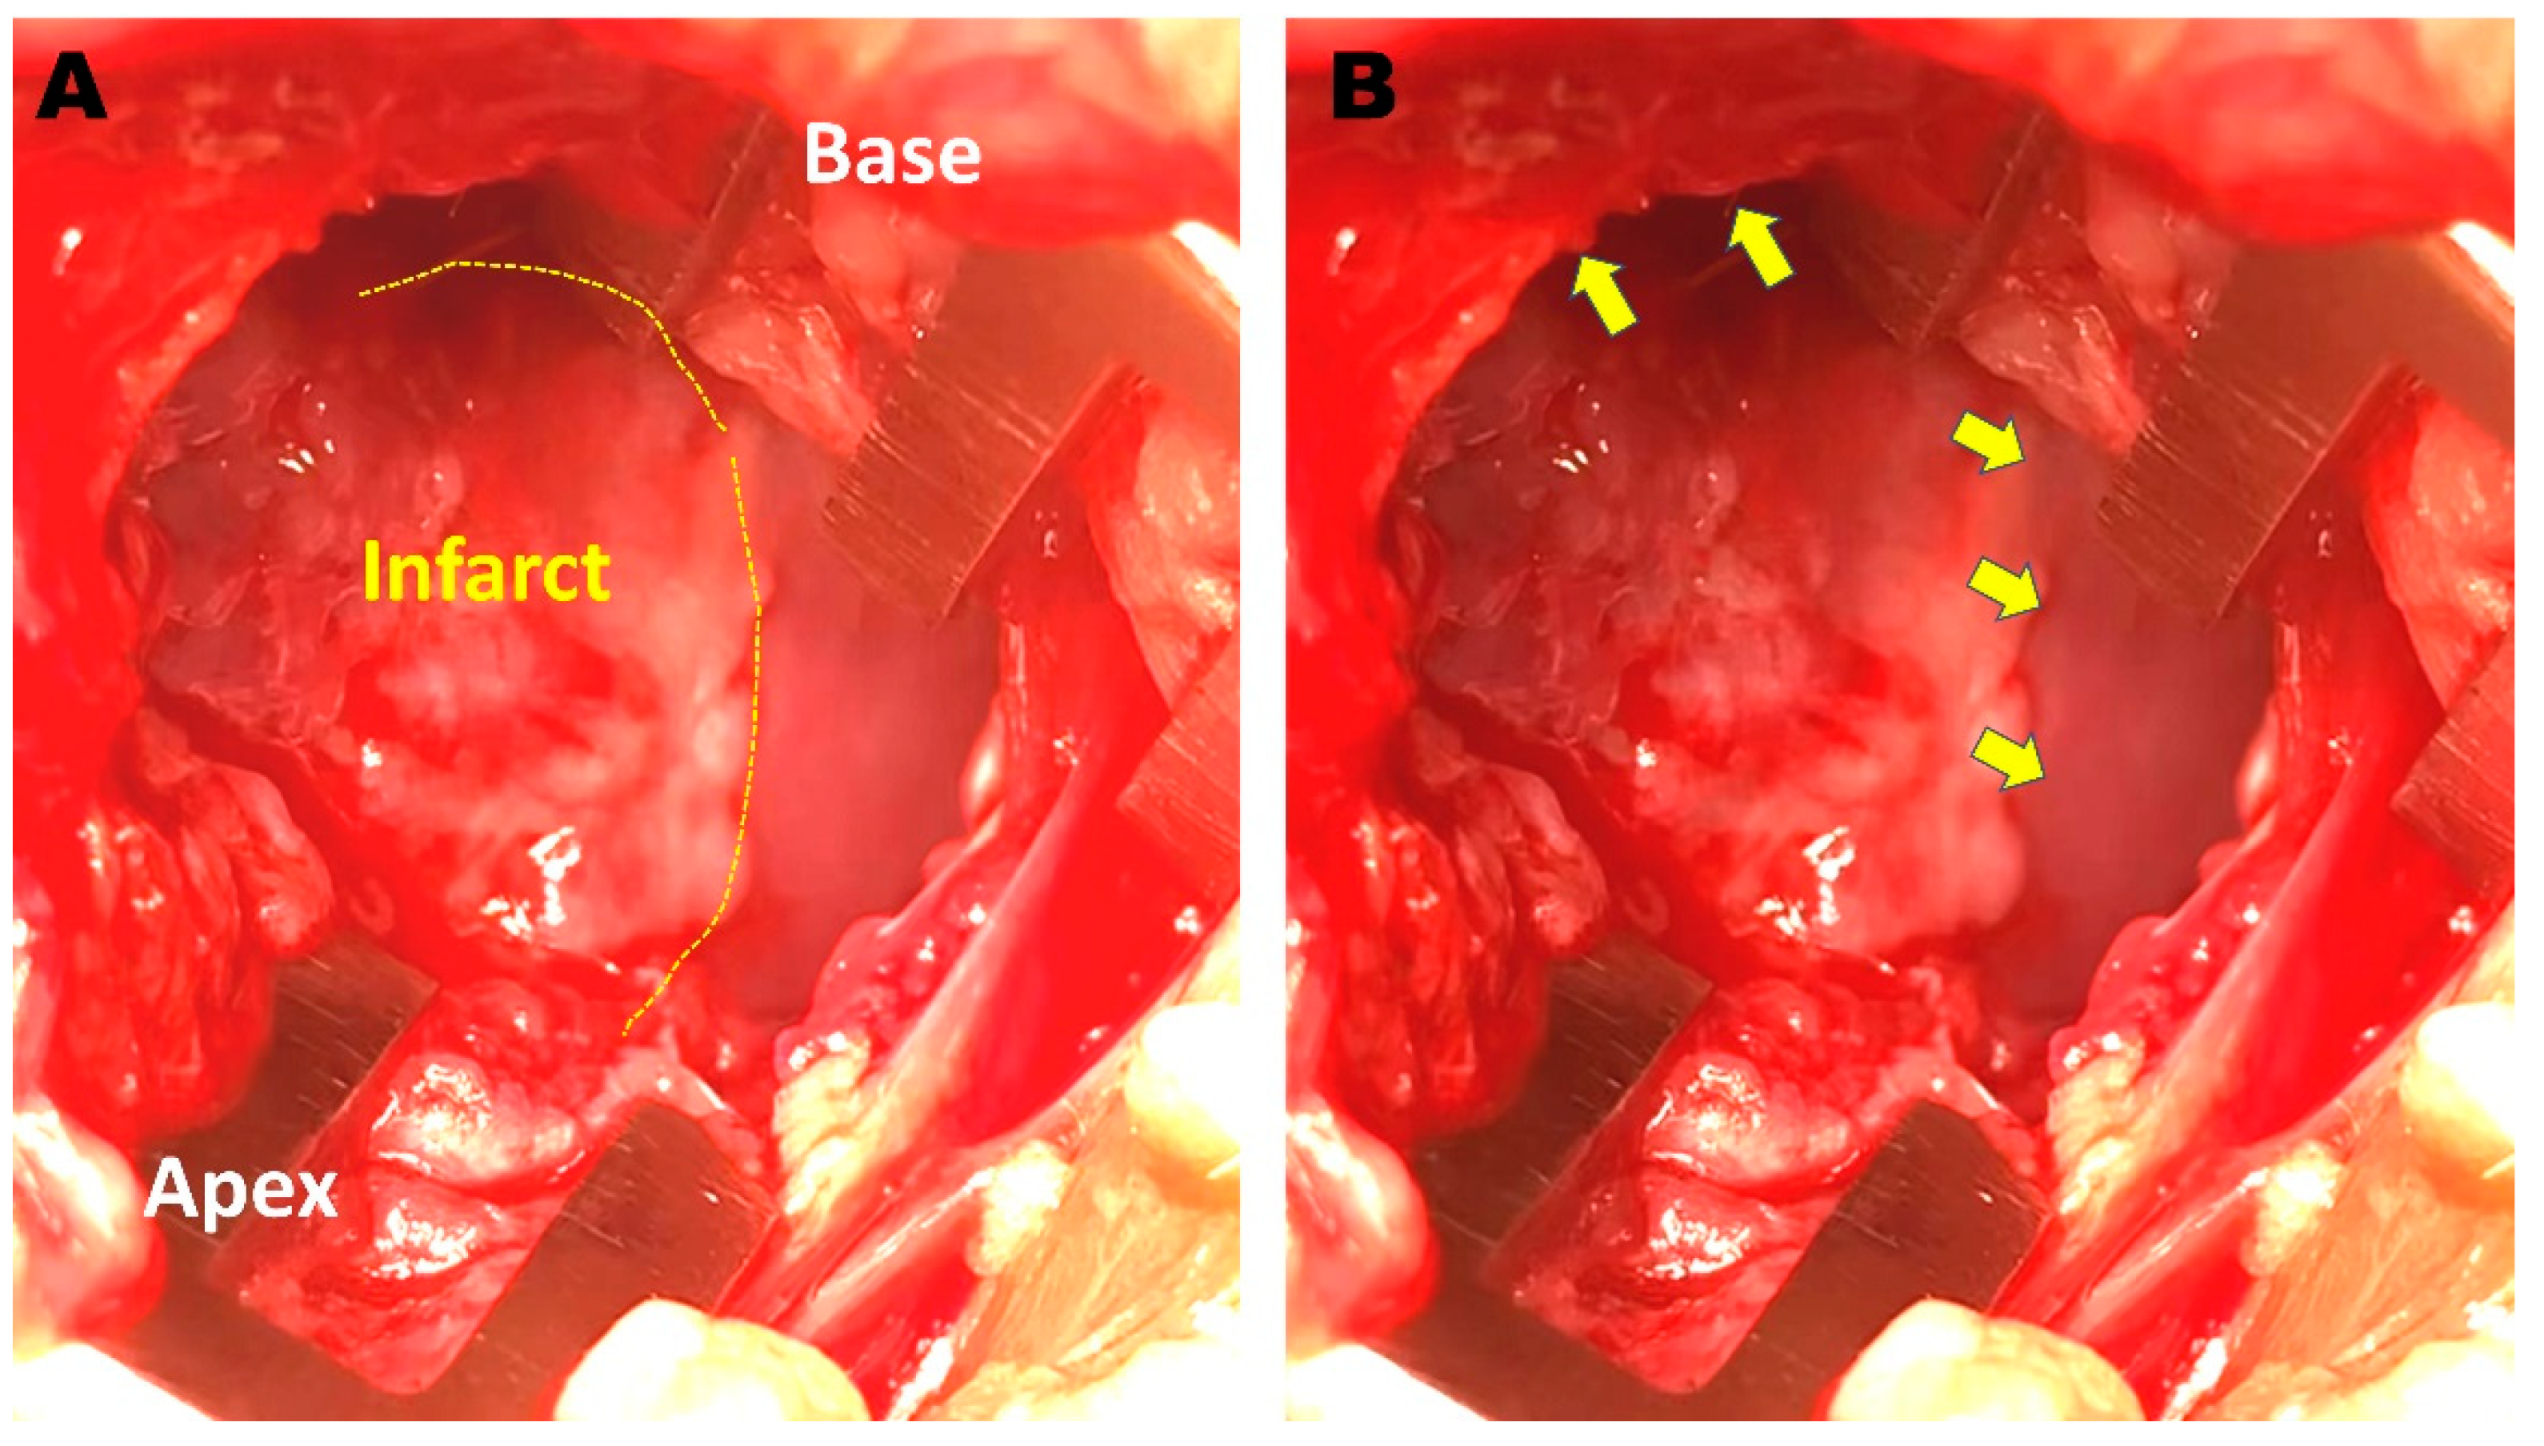

2.1. Creation of a Rabbit MI Model

2.5. Cell Injection and ILR Implantation

3.3. Histology and Cx43 Expression